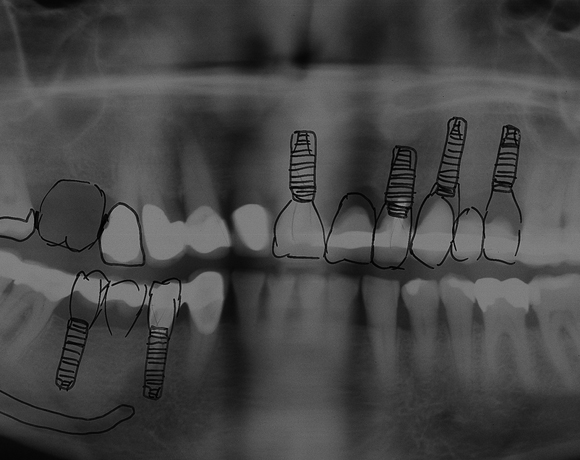

6 Implantate und viele Kronen und Brücken

Mit dem zweiteiligen vollkeramischen Implantat lassen sich auch große Lücken überbrücken.

Ein Projekt aus dem Jahr 2011

Im vorliegenden Patientenfall waren die Zähne 11 – 26 mit einer provisorischen Brücke versorgt, der Patient konnte damit aber nicht essen. Auch im Unterkiefer waren die vorhandenen Kronen und Brücken insuffizient. Es wurde eine komplette Neuversorgung für Ober- wie Unterkiefer geplant.